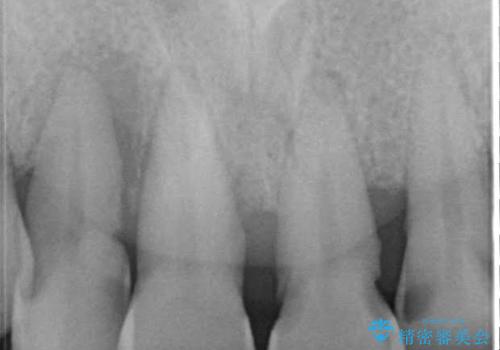

- 歯周病により欠損が生じた歯槽骨、まずは再生治療をおこなう

歯周病が進行してしまうと、歯周外科による処置が不可欠になります。

様々なリスクがありますが、唯一歯周病を除去することが可能な手段です。